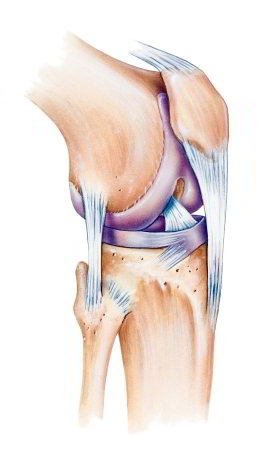

Die Kniescheibe ist neben Oberschenkel (Femur) und Schienbein (Tibia) der dritte Gelenkpartner des komplexen Kniegelenks. Sie bewegt sich im patellaren Gleitlager des Oberschenkelknochens (Trochlea) und ist sehr wichtig für die Funktion des Kniegelenks. Vor allem bei Menschen, die schwere Lasten tragen oder beruflich häufig kniend arbeiten müssen (Bodenleger, Pflasterer), wird die retropatellare Arthrose durch Druck auf die Kniescheibe wahrscheinlicher. Auch eine mangelnde Passung von Kniescheibe und ihrer Gleitrinne am Oberschenkel (Patelladysplasie) kann ursächlich sein für die Entstehung einer Arthrose. Oftmals sind auch Läufer von dem Knorpelverschleiß hinter der Kniescheibe betroffen. Zudem bekommen Frauen häufiger eine Retropatellararthrose als Männer.

Die Patella ist wichtig für die Streckbewegung (Extension) des Kniegelenks beim normalen Gehen und Stehen. Bei jeder Bewegung bewegt sich die Kniescheibe in der Gleitrinne am Kniegelenk hin und her. Auch nach Operation einer Knieprothese sind wir auf die normale Funktion der Patella angewiesen. Dabei ist sie frei an vertikal und horizontal verlaufenden Bändern aufgehängt.